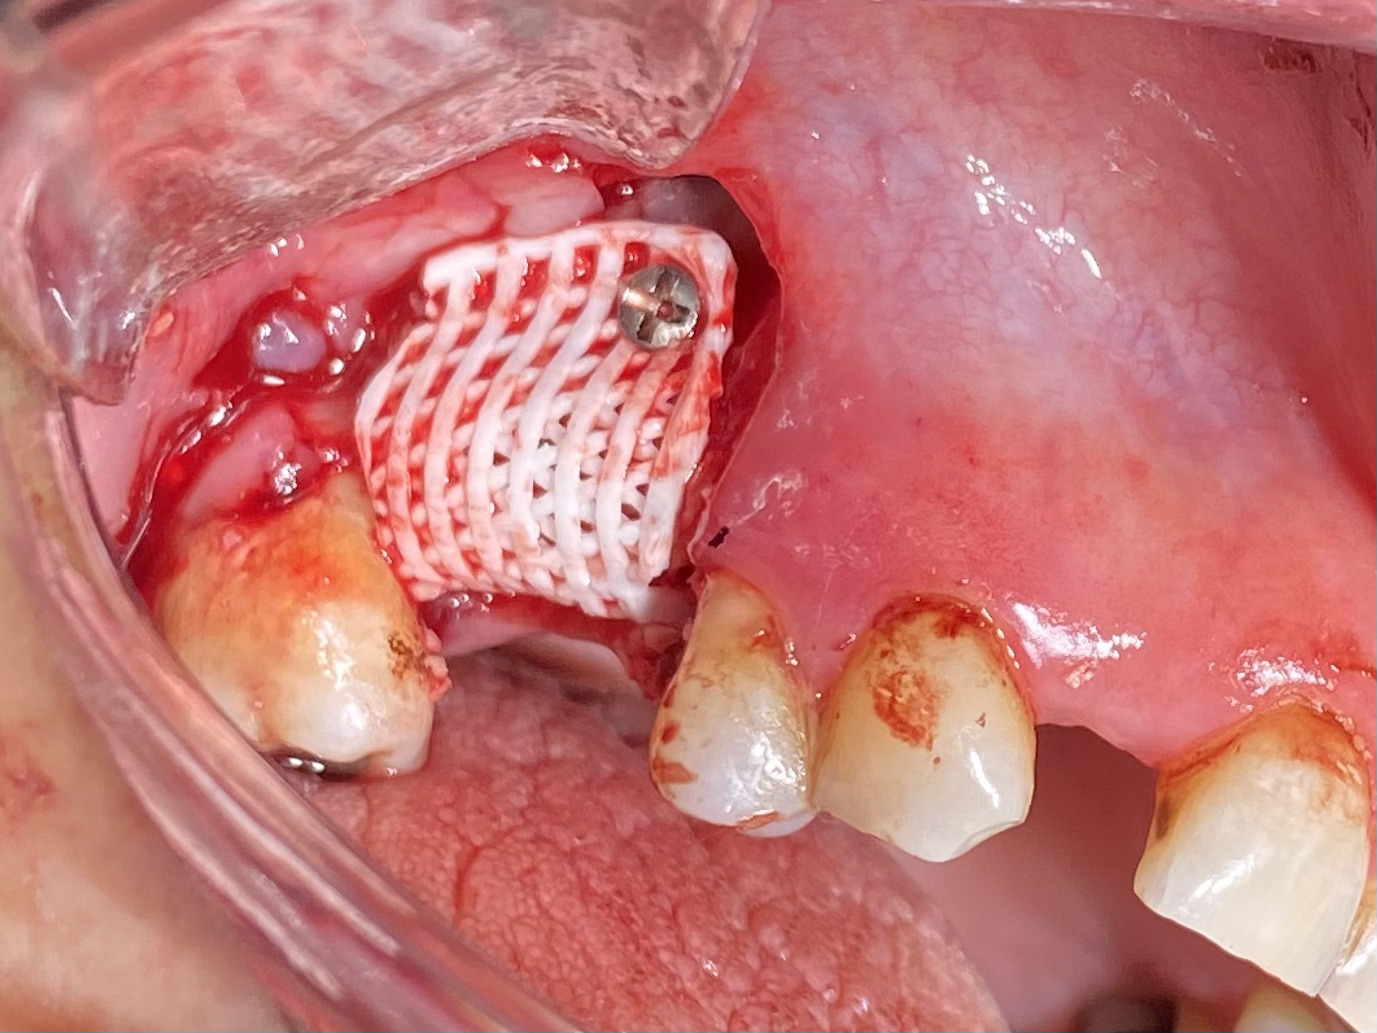

Figure 3. Graft Site after Fixation of Scaffold ( Second Patient).jpg)